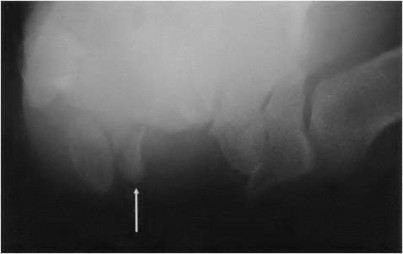

A 35-year-old woman reports wrist pain after a fall onto an outstretched hand. On exam, she has focal tenderness over the wrist snuffbox. A radiograph and CT image are shown in Figures A and B. What is the proper treatment of her injury?